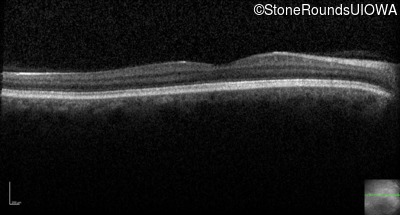

Optical Coherence Tomography - Left - 20/160 -1

Exemplar / OCT Stack